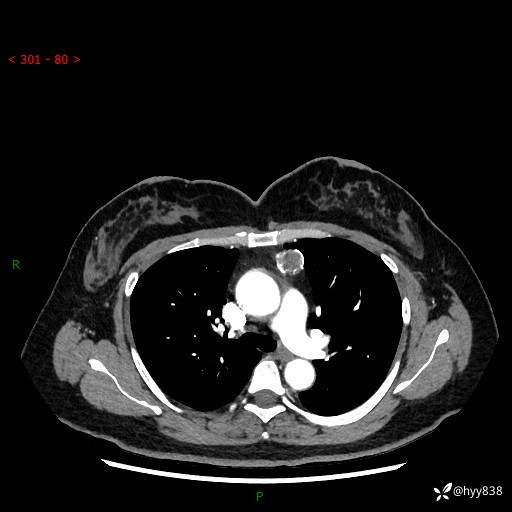

中年女性,检查发现纵隔占位3月余。圆圆的肿物,周围环绕一圈钙化---结果公布~

主诉:检查发现纵隔占位3月余。

现病史:患者于3月前体检行胸部CT检查发现纵隔占位,患者平素无明显咳嗽咳痰,无心慌、胸闷、胸痛、呼吸困难、低热、盗汗,无头痛、头晕,无腹痛、腹胀等不适。现患者欲求进一步治疗,遂来我院就诊,以“纵隔占位”收入我科。 患者自起病以来,精神可,睡眠可,饮食可,大小便正常,体重无明显改变。

胸部CT平扫+增强